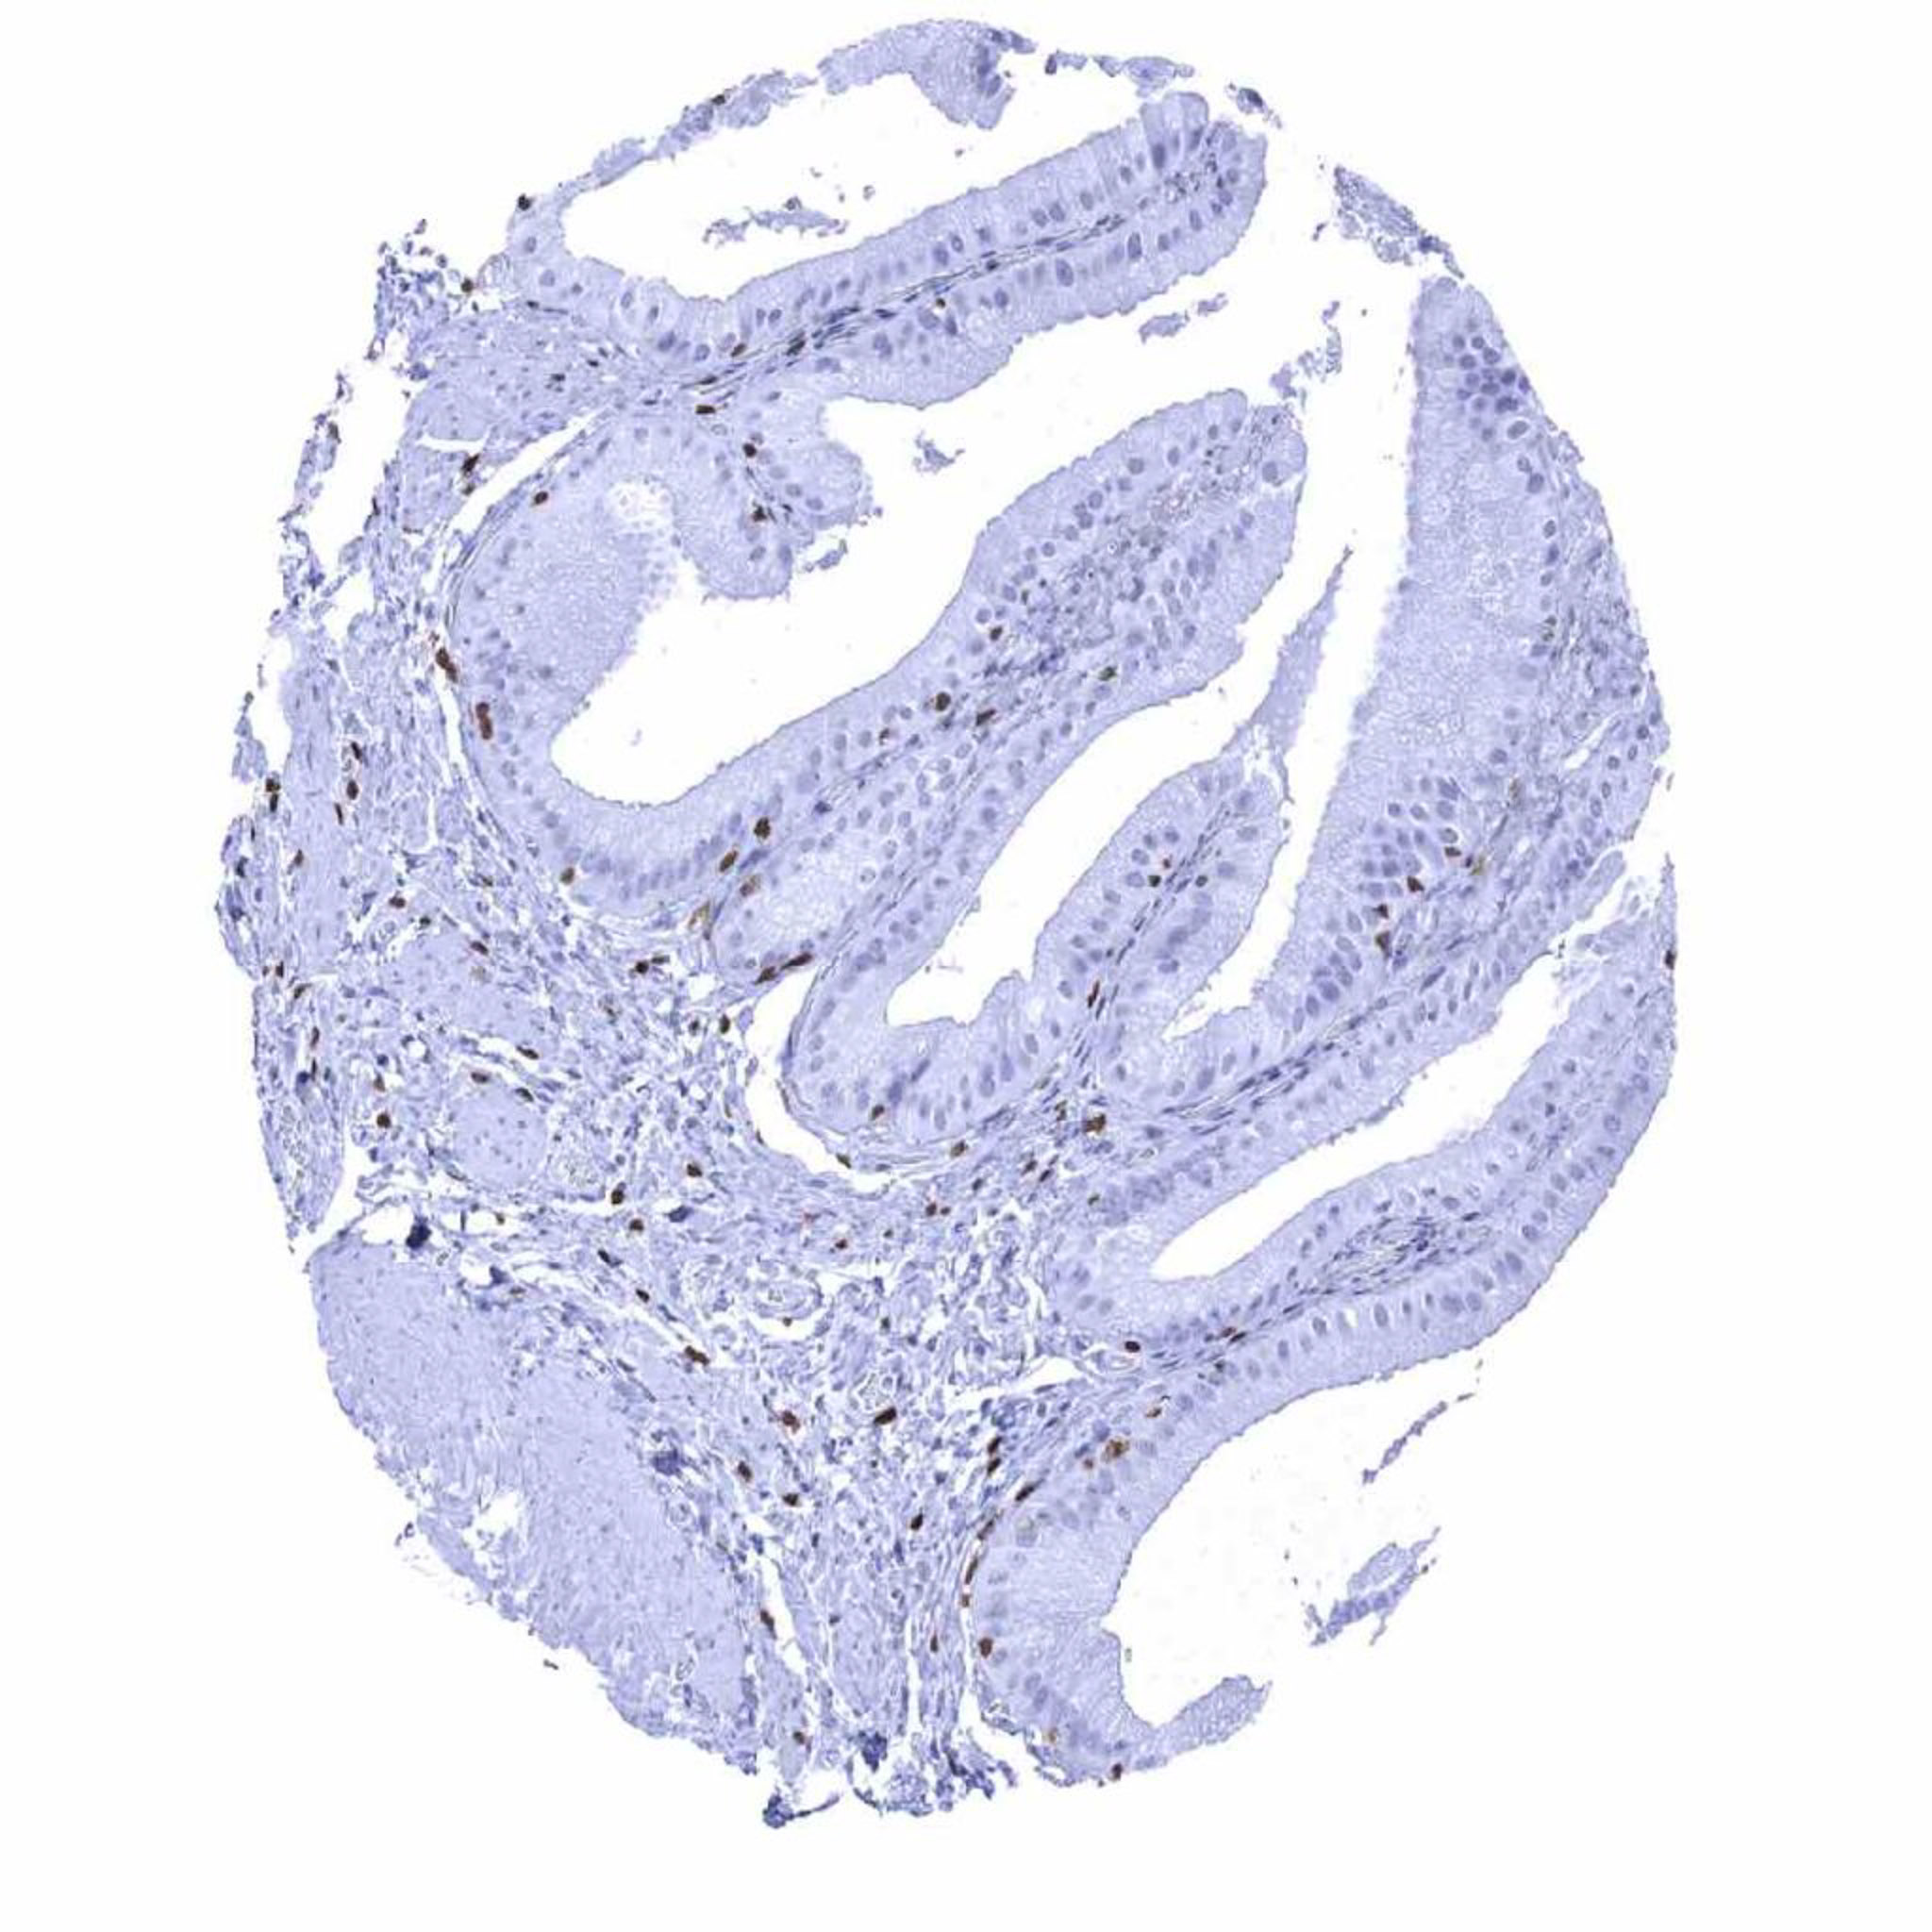

Appendix, mucosa – In the appendix, numerous ZAP70 positive lymphocytes are seen. They occur within the epithelium, in the lamina propria, and – at lower numbers – within germinal centres.